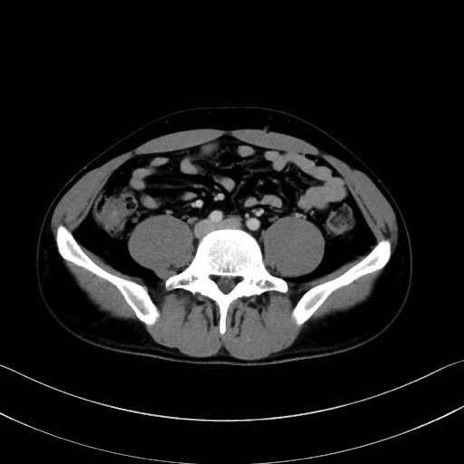

大腰筋 (Psoas major)